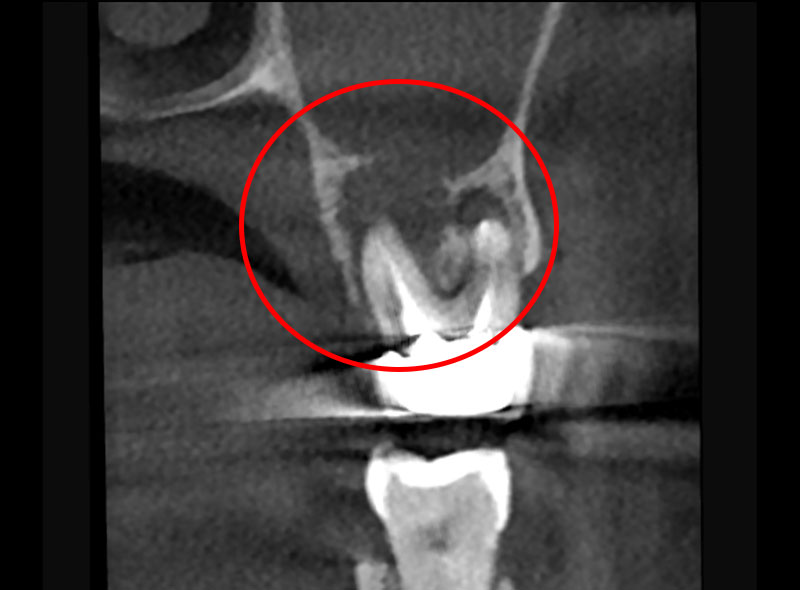

【治療例】エビデンスを重視した米国式精密根管治療

高田歯科クリニックでは、東京科学大学(旧:東京医科歯科大学)が発表した「顕微鏡を用いた歯内治療(Microendodontics)」をはじめ、高い有効性を数多く報告されている米国式精密根管治療を採用。

米国の根管治療専門医が標準的に使用する、マイクロスコープ・歯科用CT・ラバーダムに加え、歯の根(根管)の複雑な形状に対応し、柔軟な治療を可能とするニッケルチタンファイルを取り入れています。

マイクロスコープを用いて一度の処置に時間をかけて丁寧に治療することで、患部の取り残しや唾液の侵入による再感染のリスクを低減し、成功率の向上を目指すとともに、トータルの通院回数・期間の短縮にも貢献します。

術前

術後

| 症例 | 噛むと痛みがあり、他院で抜歯と言われた |

| 年齢・性別 | 40代・女性 |

| 治療期間 | 3回 |

| 治療法 | 根管治療 |

| 治療費 | 156,000円 |

| メリット | 歯を保存することができる、抜歯をしてインプラントするより費用も抑えられる |

| デメリット | 根管治療をした歯は天然歯と比べ破折のリスクがあがる |